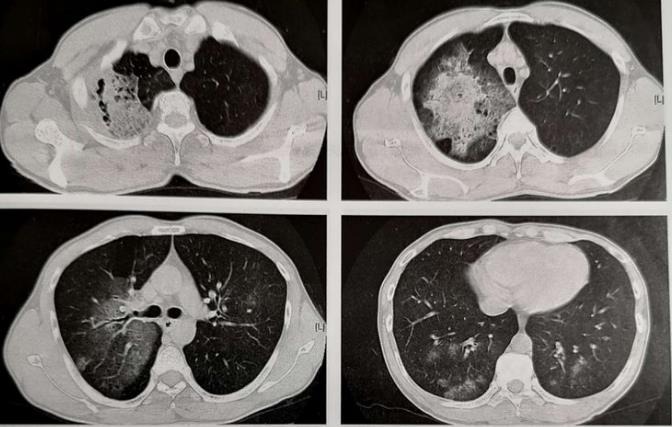

发生铜绿假单胞菌肺炎后,肺部CT会呈现什么表现?

有些病人病史和症状不典型,而这种感染需要做专业的针对性治疗,否则会有生命危险,所以CT征象很重要!

1.铜绿假单胞菌肺炎早期影像学表现与支气管肺炎相同,为双肺多发的实变影,可以按小叶、亚段或段分布,斑片状或融合灶,其病理特征是血管侵袭和坏死,可见微脓肿、出血和局灶性坏死,所有肺叶均可受累,但其所致社区获得性肺炎以右肺上叶受累为主。

2.某些不常见的影像学表现,可以呈现大叶性实变,多发结节状阴影或网格状表现,需要密切结合病史。

就像这位老爷子,有多年的支气管炎肺气肿,肺部免疫力减退,感染铜绿后发生右上肺为主的病灶,已经融合为大片实变,边缘有模糊的磨玻璃影,内部有坏死和小空洞提示为化脓性炎。后来确诊为铜绿假单胞菌肺炎,因为诊断及时,用药合理,抢救成功了!

这类病人在临床表现常为突然发病,伴有寒战,发热和严重的呼吸困难,咳黄色或黄绿色脓性痰,原有肺部慢性疾病的病人,平时常伴有慢性咳嗽咳痰,当出现黄绿色脓痰,呼吸困难加重及肺功能进行性减退时,应考虑铜绿假单胞菌感染的可能,要及时正确诊治!